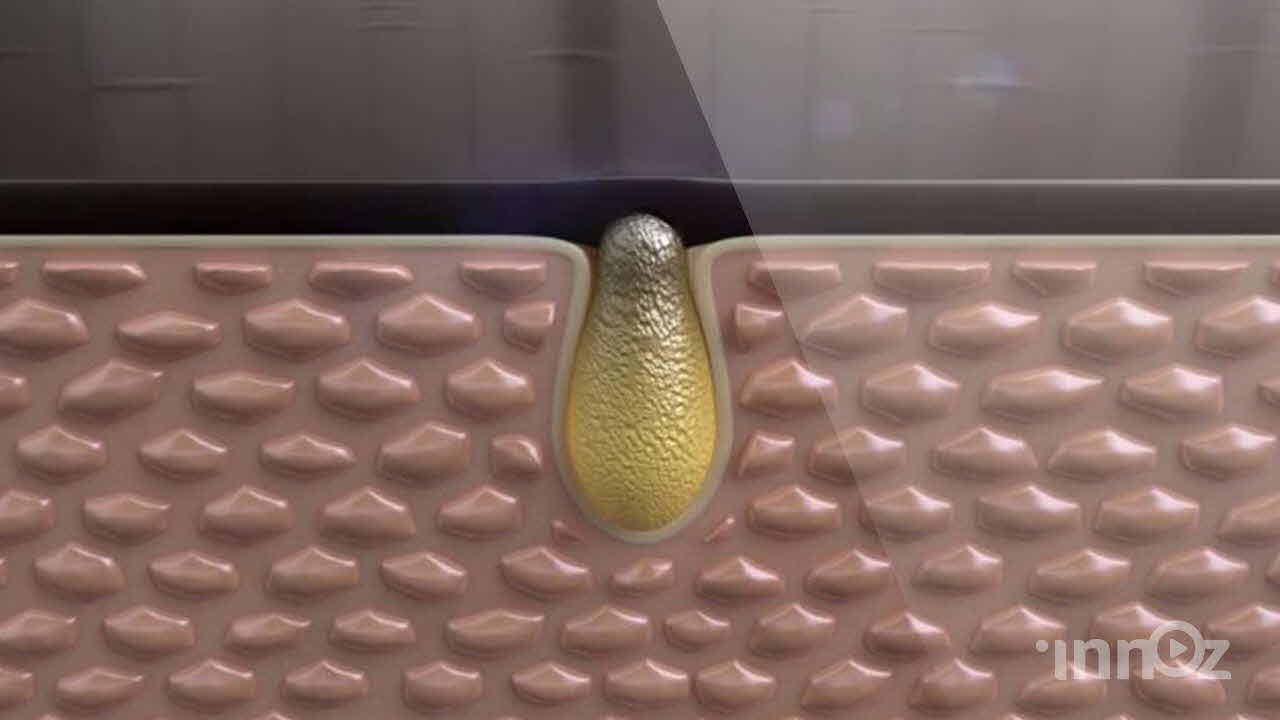

의료, 건설, 산업, VR AR, AI 등 고퀄리티 3D영상제작

이노즈는 AI영상제작, 3D영상 제작 전문기업으로, 다양한 산업 분야에 걸쳐 혁신적이고 몰입감 있는 3D 콘텐츠를 제공합니다. 제품 홍보, 건설 시뮬레이션, 애니메이션 등 맞춤형 영상으로 고객사의 가치를 시각적으로 효과적으로 전달합니다. 고품질의 3D 시각화와 창의적인 연출을 바탕으로, 고객의 목표를 실현하는 독창적이고 강력한 시각적 경험을 제공합니다. 이노즈의 포트폴리오는 고객의 아이디어를 현실로 구현한 다양한 성공적인 프로젝트로 가득합니다.

2023 쉬엔비 다이아코어등 고주파 치료기 전제품

2023 제이시스메디칼 고주파치료기 덴서티 영상제작

2022 텐텍 텐써마 고주파 의료장비 영상제작

2022 시지바이오 페이스템 필러 의료 영상제작

2020 파마리서치프로덕트 무릎관절손상 영상제작

2020 삼진제약 암세포제거 영상제작

2019 짐머바이오메트코리아 의료용 영상제작